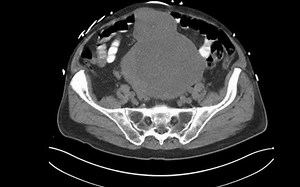

What is a GIST Tumor